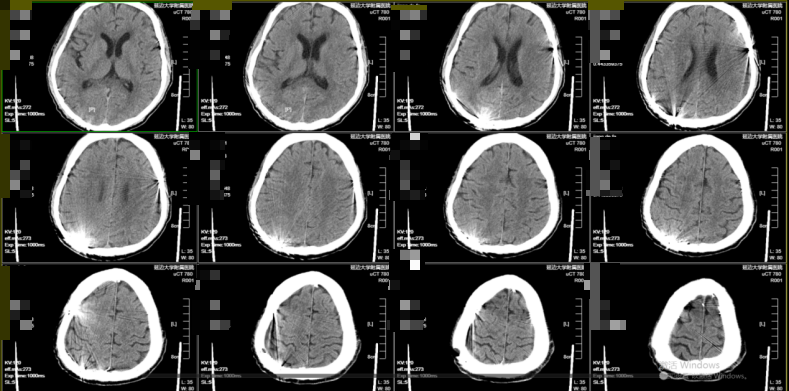

考虑患者高龄、基础状态差,特别是既往肝癌手术(影响凝血因子合成)及脾脏切除(可导致血小板计数及功能异常)导致的凝血功能紊乱,保守治疗风险极高且效果较差。黄宪主任医师、马吉男主治医师团队果断行右侧颅骨钻孔引流术(左侧给予保守治疗),术后瞳孔回缩,意识转清。术后密切监测病情变化。考虑其脾切除后存在凝血机制异常,血肿复发概率高,与家属沟通后进一步行经导管双侧脑膜中动脉(MMA)栓塞术,从而降低复发率。术后神清语明,四肢无瘫,顺利出院。1个月后复查头部CT右侧慢性硬膜下血肿明显减少,左侧慢性硬膜下血肿基本吸收。四肢肢体肌力V级。事实证明,经导管双侧脑膜中动脉(MMA)栓塞术治疗慢性硬膜下血肿效果显著,且依据文献报道可将复发率降至5%以下。

图2钻孔引流术后

图3经导管脑膜中动脉(MMA)栓塞术后

图4、1个月后复查头部CT